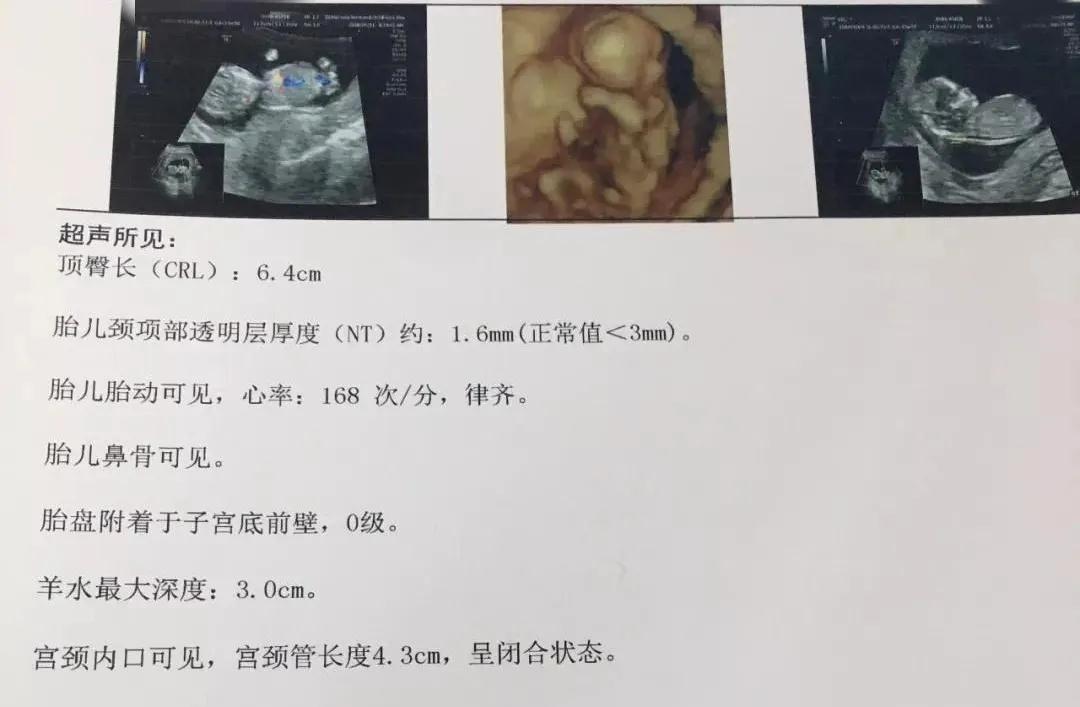

NT是胎儿颈部半透明膜的缩写,是10~13孕周围绕在胎儿颈项后部流动性的半透明蛋白膜。它的厚度与胎儿DS缺陷正相关,并可以通过超声成像测量。

NT排畸检查是指胎儿颈后部皮下组织内液集聚的厚度的检查。通过B超测定颈项透明层厚度,便于及早发现唐氏儿和先天性心脏病的胎儿,并及时予以干预。

NT增厚越明显,胎儿异常机会就越高,异常程度也会越严重。一般正常的NT厚度不能大于3mm,当大于3mm时约10%会发育为异常胎儿;当大于6mm时,这个异常程度会大大增加,约90%会发育成异常胎儿。